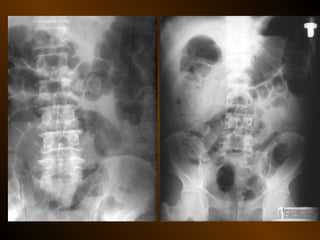

CĂNG GIÃN ỐNG TIÊU HÓA

PHÂN BIỆT

RUỘT NON – ĐẠI TRÀNG

• Các nếp Kerckring

• Nếp ngấn thanh mạc

• Khẩu kính

• Số lượng quai

• Phân bố các quai ruột

• Cao / rộng

• Chất cặn bã